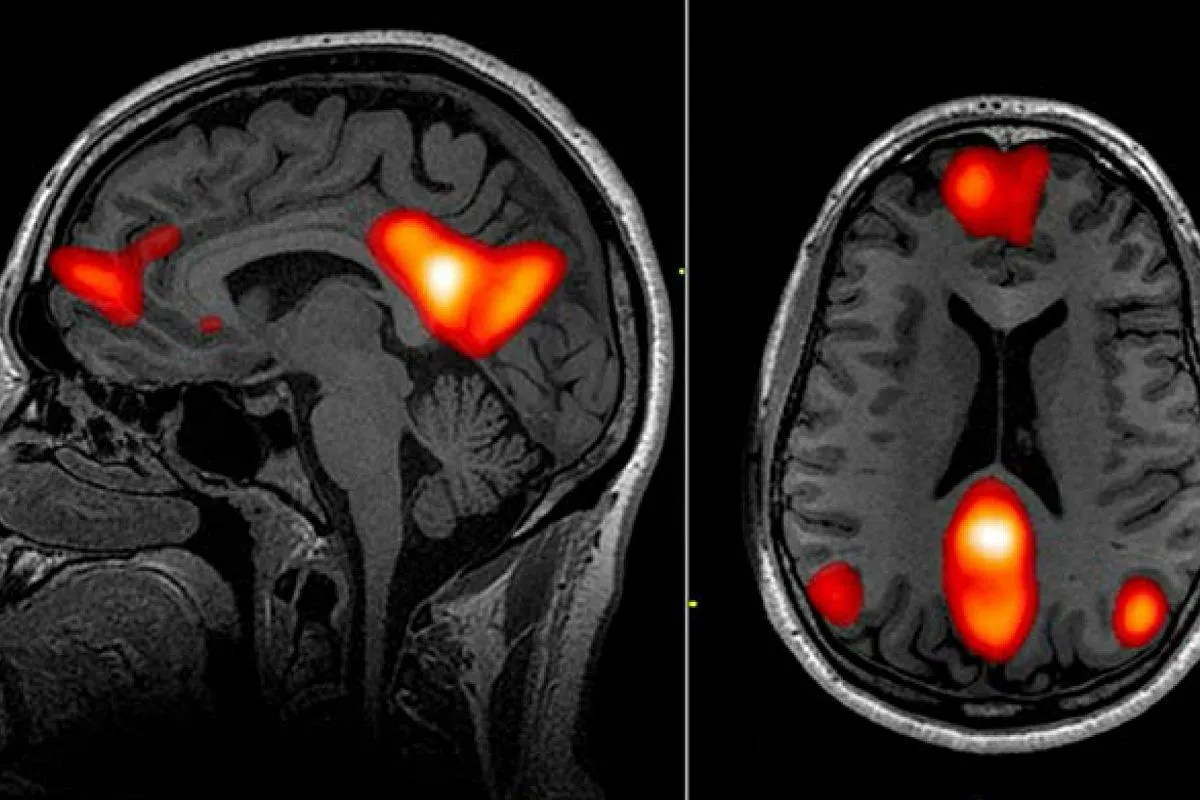

Wyobraź sobie swój mózg jako mięsień, który potrzebuje regularnego treningu. Czytanie to jedna z najlepszych form takiej aktywności. Badania z wykorzystaniem rezonansu magnetycznego (fMRI) jednoznacznie pokazują, że podczas lektury aktywuje się wiele obszarów mózgu, a wzmożona łączność neuronalna utrzymuje się nawet przez kilka dni po zakończeniu książki. To nie tylko stymuluje neuroplastyczność, czyli zdolność mózgu do tworzenia nowych połączeń, ale także wzmacnia istniejące. To fascynujące, jak prosta czynność może tak intensywnie wpływać na naszą strukturę poznawczą.